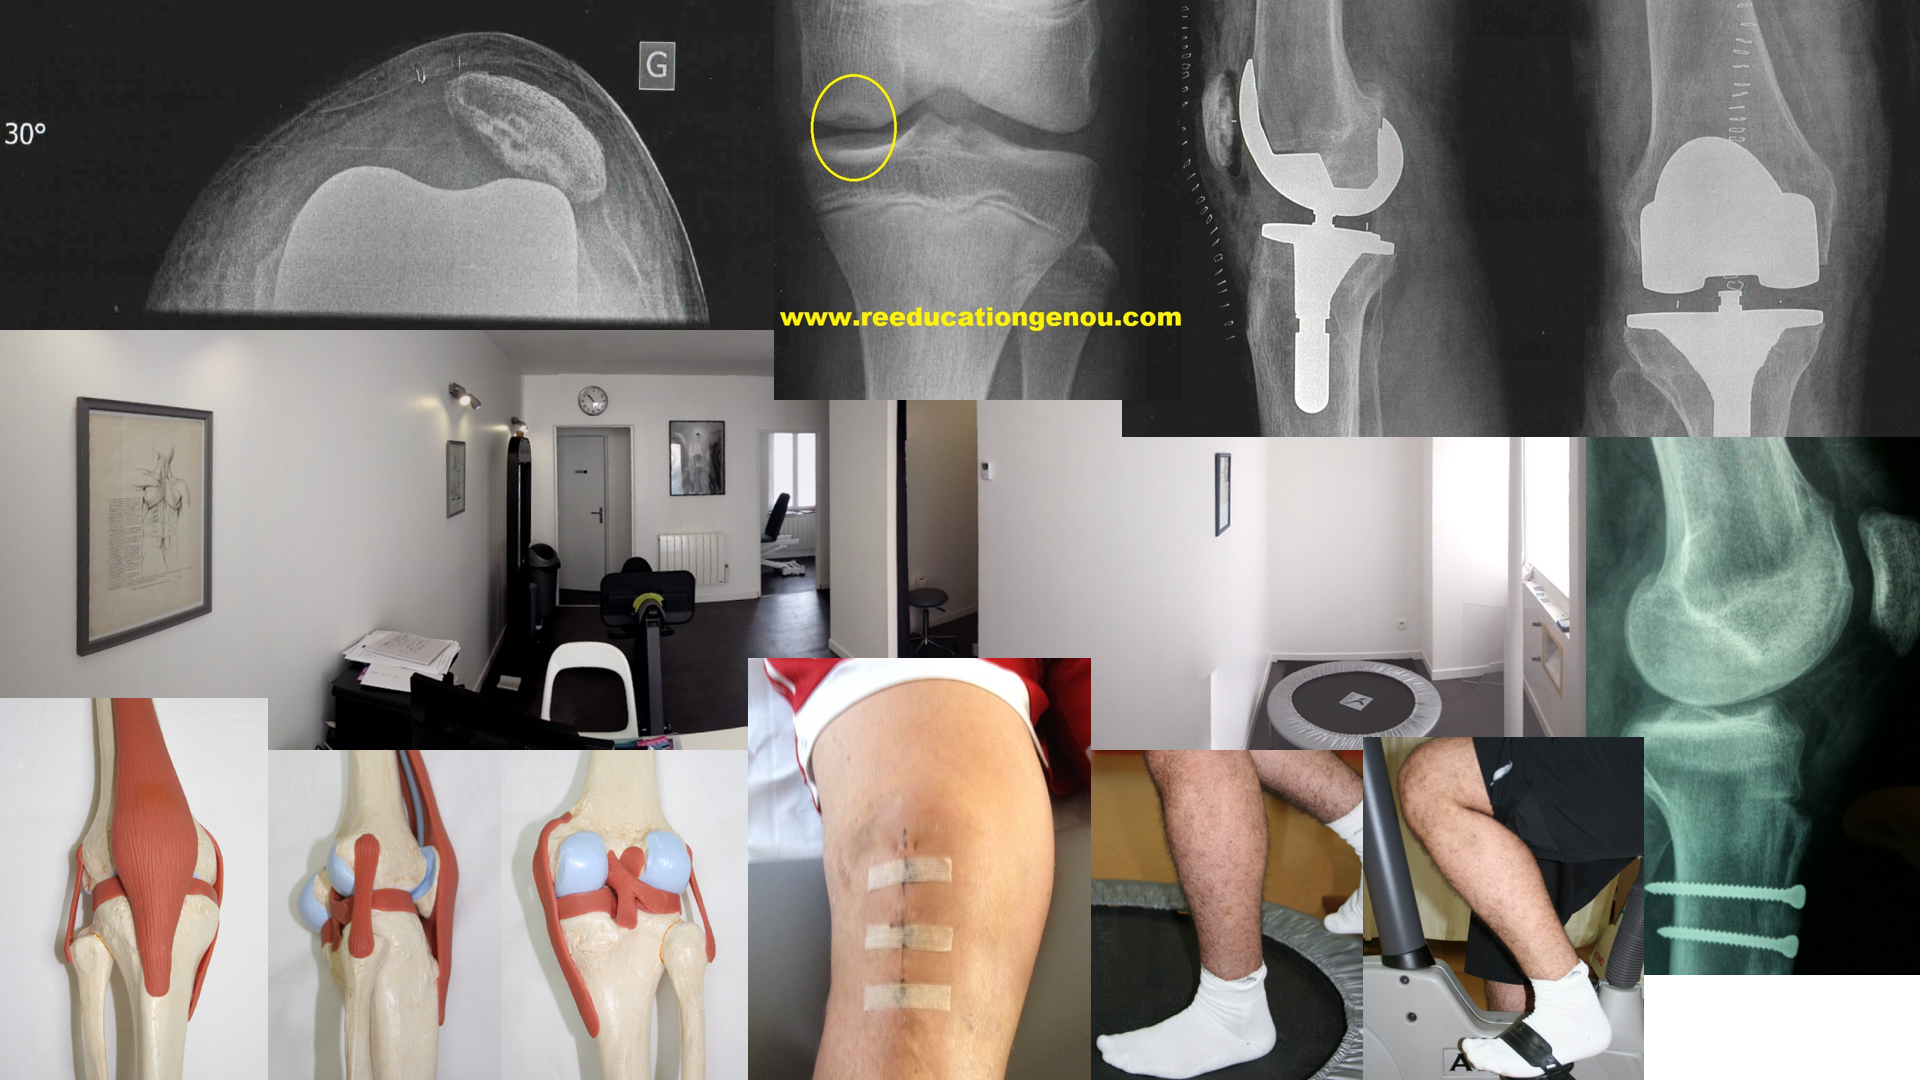

Prothese Du Genou Nouvelle Generation 2021 Reeducationgenou.com - prothèse genou